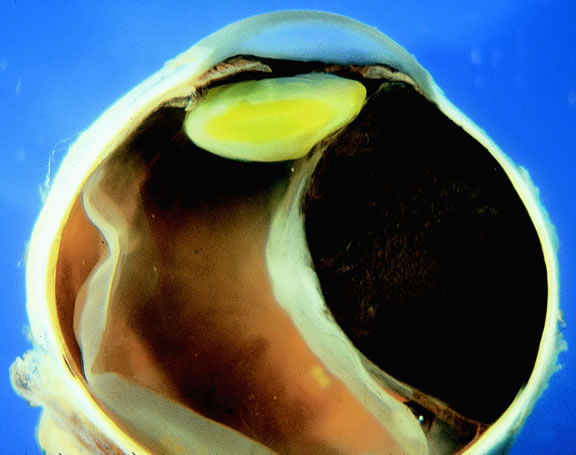

Many choroidal melanomas have a characteristic mushroom or collar button configuration that results when the tumor breaks through Bruch's membrane (Figs. 19, 20, 21, and 22). In such cases there is often secondary choroidal, subretinal, or vitreous hemorrhage. Dilated, intrinsic vessels often are evident in the mushrooming dome of nonpigmented melanomas. The vessels are obscured in more pigmented tumors.48

Fig. 20. Gross photo of mushroom-shaped choroidal melanoma. Amelanotic dome of melanoma anterior to break in Bruch's membrane elevates and detaches retina. Mushrooming head of tumor has a rough papillary surface and contains many vessels.

Fig. 21. Gross photo, large mushroom-shaped ciliochoroidal melanoma. Pigmented tumor is highly elevated.

Gross Pathology

Choroidal melanomas initially arise in the stroma of the choroid. In early cases, the profile of the sectioned tumor is oval or almond-shaped, and its tissue usually appears relatively cohesive after fixation (Fig. 24). Although some tumors diffusely infiltrate the uvea, most uveal melanomas are relatively well-circumscribed tumors with distinct margins. In many cases the growing melanoma perforates Bruch's membrane and enters the subretinal space where its apex typically assumes a spherical shape that often is likened to a mushroom or collar button (see Figs. 19 to 22.). Dilated vessels often are found in the mushrooming head of the tumor because the ends of Bruch's membrane exert a compressive cinch-like effect on the waist of the tumor (see Fig. 22). Rupture of Bruch's membrane was present in 87.7% of 1527 large- or medium-sized melanomas examined in the COMS.84 Retinal invasion was present in nearly half (49.1%), and tumor cells were found in the vitreous body in one fourth.

Fig. 24. Cut surface of heavily pigmented choroidal melanoma is almond-shaped. Bruch's membrane is intact.

Uveal melanomas vary markedly in their pigment content. Some tumors are totally amelanotic; others are maximally pigmented. In some instances, distinct clones of tumor cells that vary in pigment content are evident on gross examination or even clinically (Fig. 25). A friable or granular appearance of the cut surface of a melanoma noted during gross examination may be indicative of necrosis or a tumor rich in poorly cohesive epithelioid cells. Melanomas that contain cystic cavities occasionally are encountered.85

Fig. 25. Large dome-shaped ciliochoroidal melanoma is partially amelanotic. Bruch's membrane is intact.